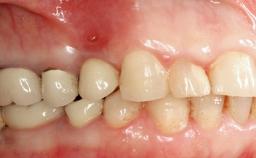

In 2004, the patient, a smoker, began dental treatment at the ACTA graduate clinic. She was a TV producer exposed to a lot of stress in her job and had a sick husband. Her maxillary teeth had been extracted, as had the mandibular canines, premolars, and molars, with the exception of tooth 34. She received a complete maxillary denture and a mandibular skeleton denture. In October 2007, her maxilla was augmented by an oral and maxillofacial surgeon; in March 2008, implants (Biomet 3i, Palm Beach, Florida, USA) were inserted at that same clinic. In 2008, the patient was presented at the Department of Oral Implantology and Prosthetic Dentistry to request restorations for her implants. An implant-supported overdenture was planned. She also asked if we could restore her occlusion with fixed prosthetics.